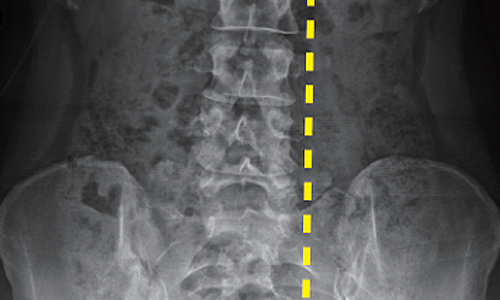

Before & After 척추측만증 교정 사례

• 30대 직장인

치료기간 3개월

BEFORE

AFTER